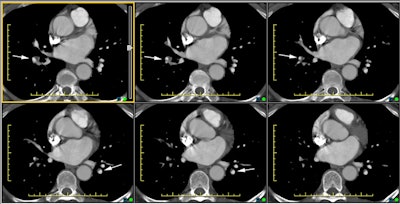

The CT scan below is from a patient with chronic pulmonary embolism. The white arrows denote vessels with thrombus that is eccentric and has been incorporated into the vessel walls.